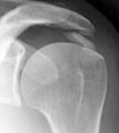

LES RADIOGRAPHIES SIMPLES

On utilisera le plus fréquemment des incidences de face sous plusieurs rotations (rotation interne, rotation zéro, rotation externe), et certaines incidences de profil, différentes selon l’origine de la pathologie (profil axillaire, ou encore profil de glène).